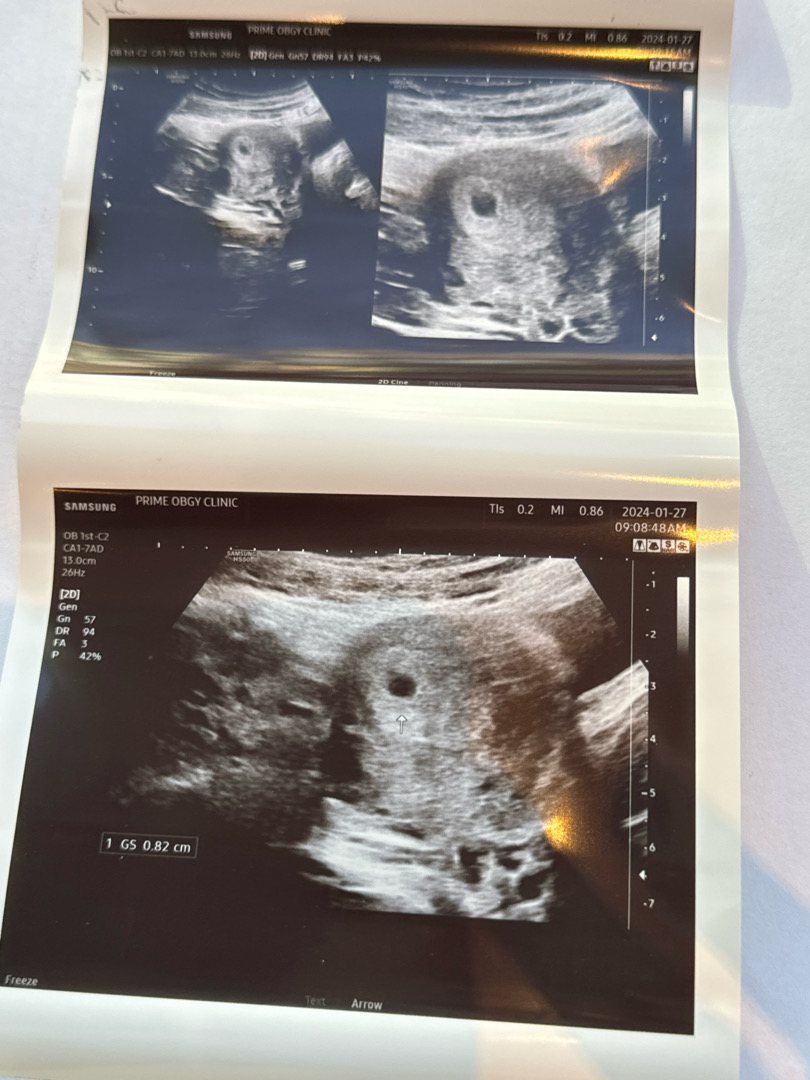

오늘 드디어 아기집 보구 왔어요 !! 🏠

어플로는 5주 5일인데 배초음파보니 5주 0일이라 하시고 아기집 크기는 0.82cm라고 하네요 ! 상부쪽에 자리 예쁘게 잘 잡고 피고임도 없다고 해서 안심하고 왔어요 ㅠㅠ 🥹 수첩 받았는데 이 마음 무슨 느낌이쥬!? ♥️

우왕 우왕 저랑 비슷하네요 ! 전 오늘 27일이 5주 0일이라고 하시더라구용 ! ㅎㅎㅎㅎ 아기집 크기는 0.82cm 라고 하셨어용 얼른 심소 들었으면 좋겠어요 >_< 😍